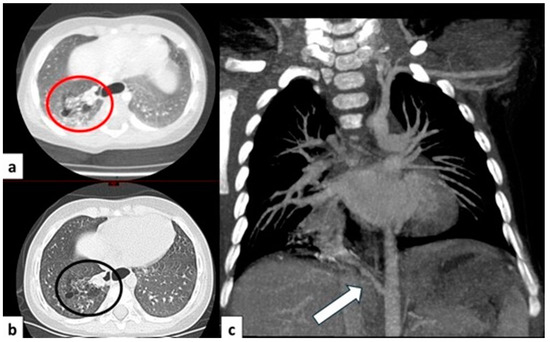

3.6.1. Pulmonary Sequestration